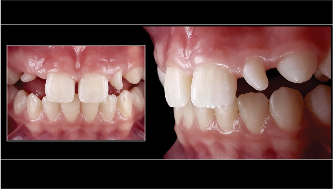

Fig 4. Left: This intraoral photograph taken with only a smartphone shows image distortion and poor color rendering. Right: This intraoral photograph was taken with a DSLR camera with an external flash and is much higher quality.

Figure 4